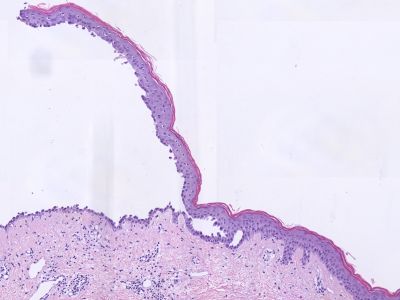

Aanvullend onderzoek:

Histologie (biopt met daarin een randje van de blaar voor

HE, de IF uit de normale peri-lesionale huid); vroeg stadium: spongiotische

dermatitis met oedeem vooral laag in de epidermis. Later suprabasale acantholyse

met vorming van intra-epidermale splijting en blaren, ook in de follikels. Basale

cellen splijten van elkaar, niet van de basale laag waardoor de basale keratinocyten

een 'thombstone' (grafstenen) aspect hebben. De blaarholte bevat acantholytische

keratinocyten, fibrine, en eosinofiele granulocyten. Geen / weinig dyskeratotische

cellen. Dermis: superficieel gemengdcellig perivasculair en interstitieel infiltraat

met veel eosinofiele granulocyten.